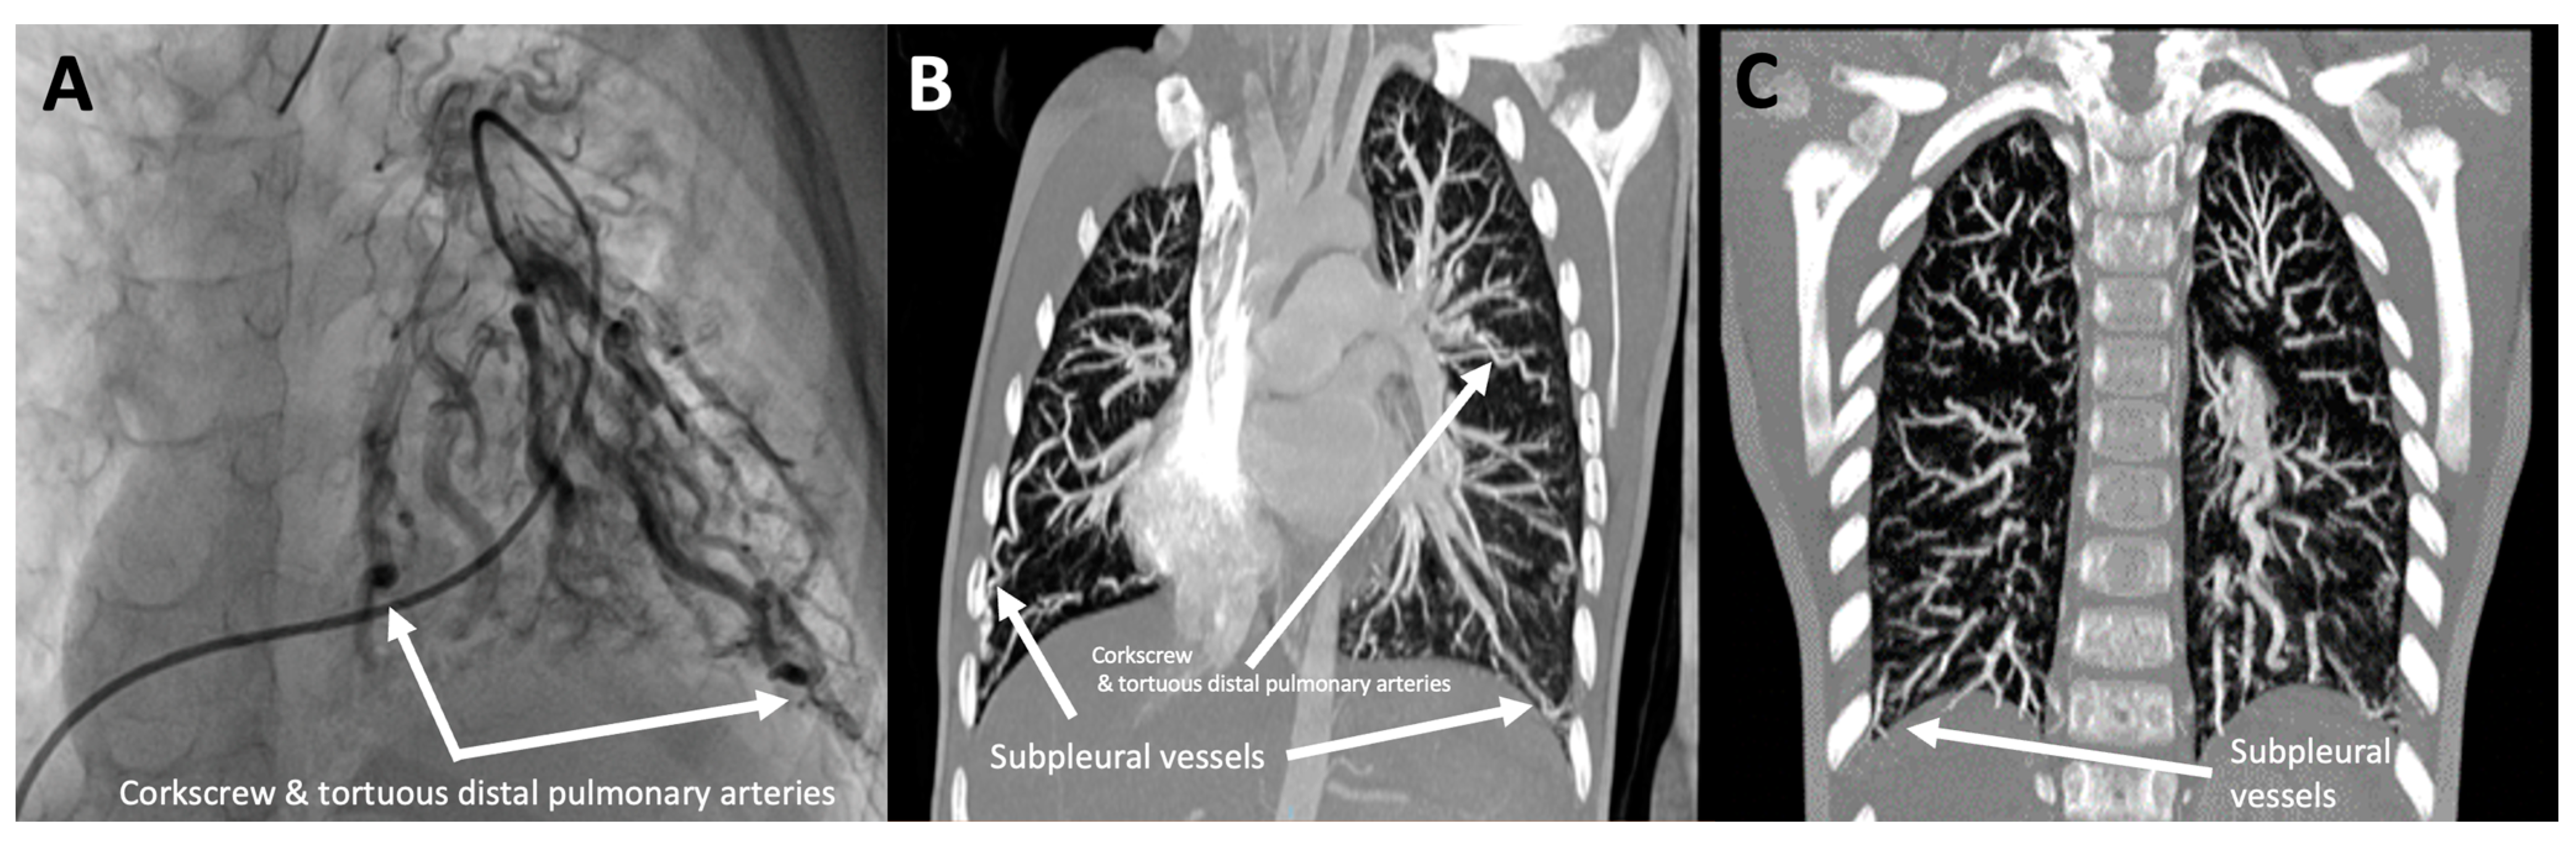

3.1.2. Patient 2